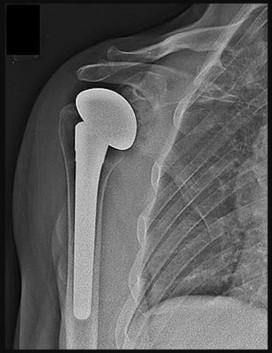

A 70-year-old man has a 1-year history of progressive right shoulder pain, motion loss, and weakness associated with rotator cuff arthropathy. He has failed nonsurgical treatment. During the informed consent process, the patient is counseled regarding his treatment options, and the surgeon recommends that he undergo a right reverse total shoulder arthroplasty (rTSA). The patient must be informed about the complications associated with this type of procedure, the most common of which is

rTSA originally was used to address rotator cuff arthropathy. Current indications have expanded to include massive rotator cuff tears without arthritis, failed shoulder arthroplasty, 3- and 4-part proximal humerus fractures, and glenohumeral arthrosis associated with severe/uncorrectable glenoid retroversion. rTSA volume has increased, leading to identification of problems specific to the procedure. Some of the common complications include neurologic injury, periprosthetic fracture, hematoma, infection, scapular notching, prosthetic joint instability, baseplate failure, and acromial fracture. A meta-analysis performed by Bohsali and associates involving rTSA

demonstrated these complications in decreasing order of frequency: scapular notching, hematoma formation, glenoid dissociation such as baseplate failure or aseptic loosening, glenohumeral dislocation, acromial and/or scapular spine fracture, infection, loosening or dissociation of the humeral component, and nerve injury.